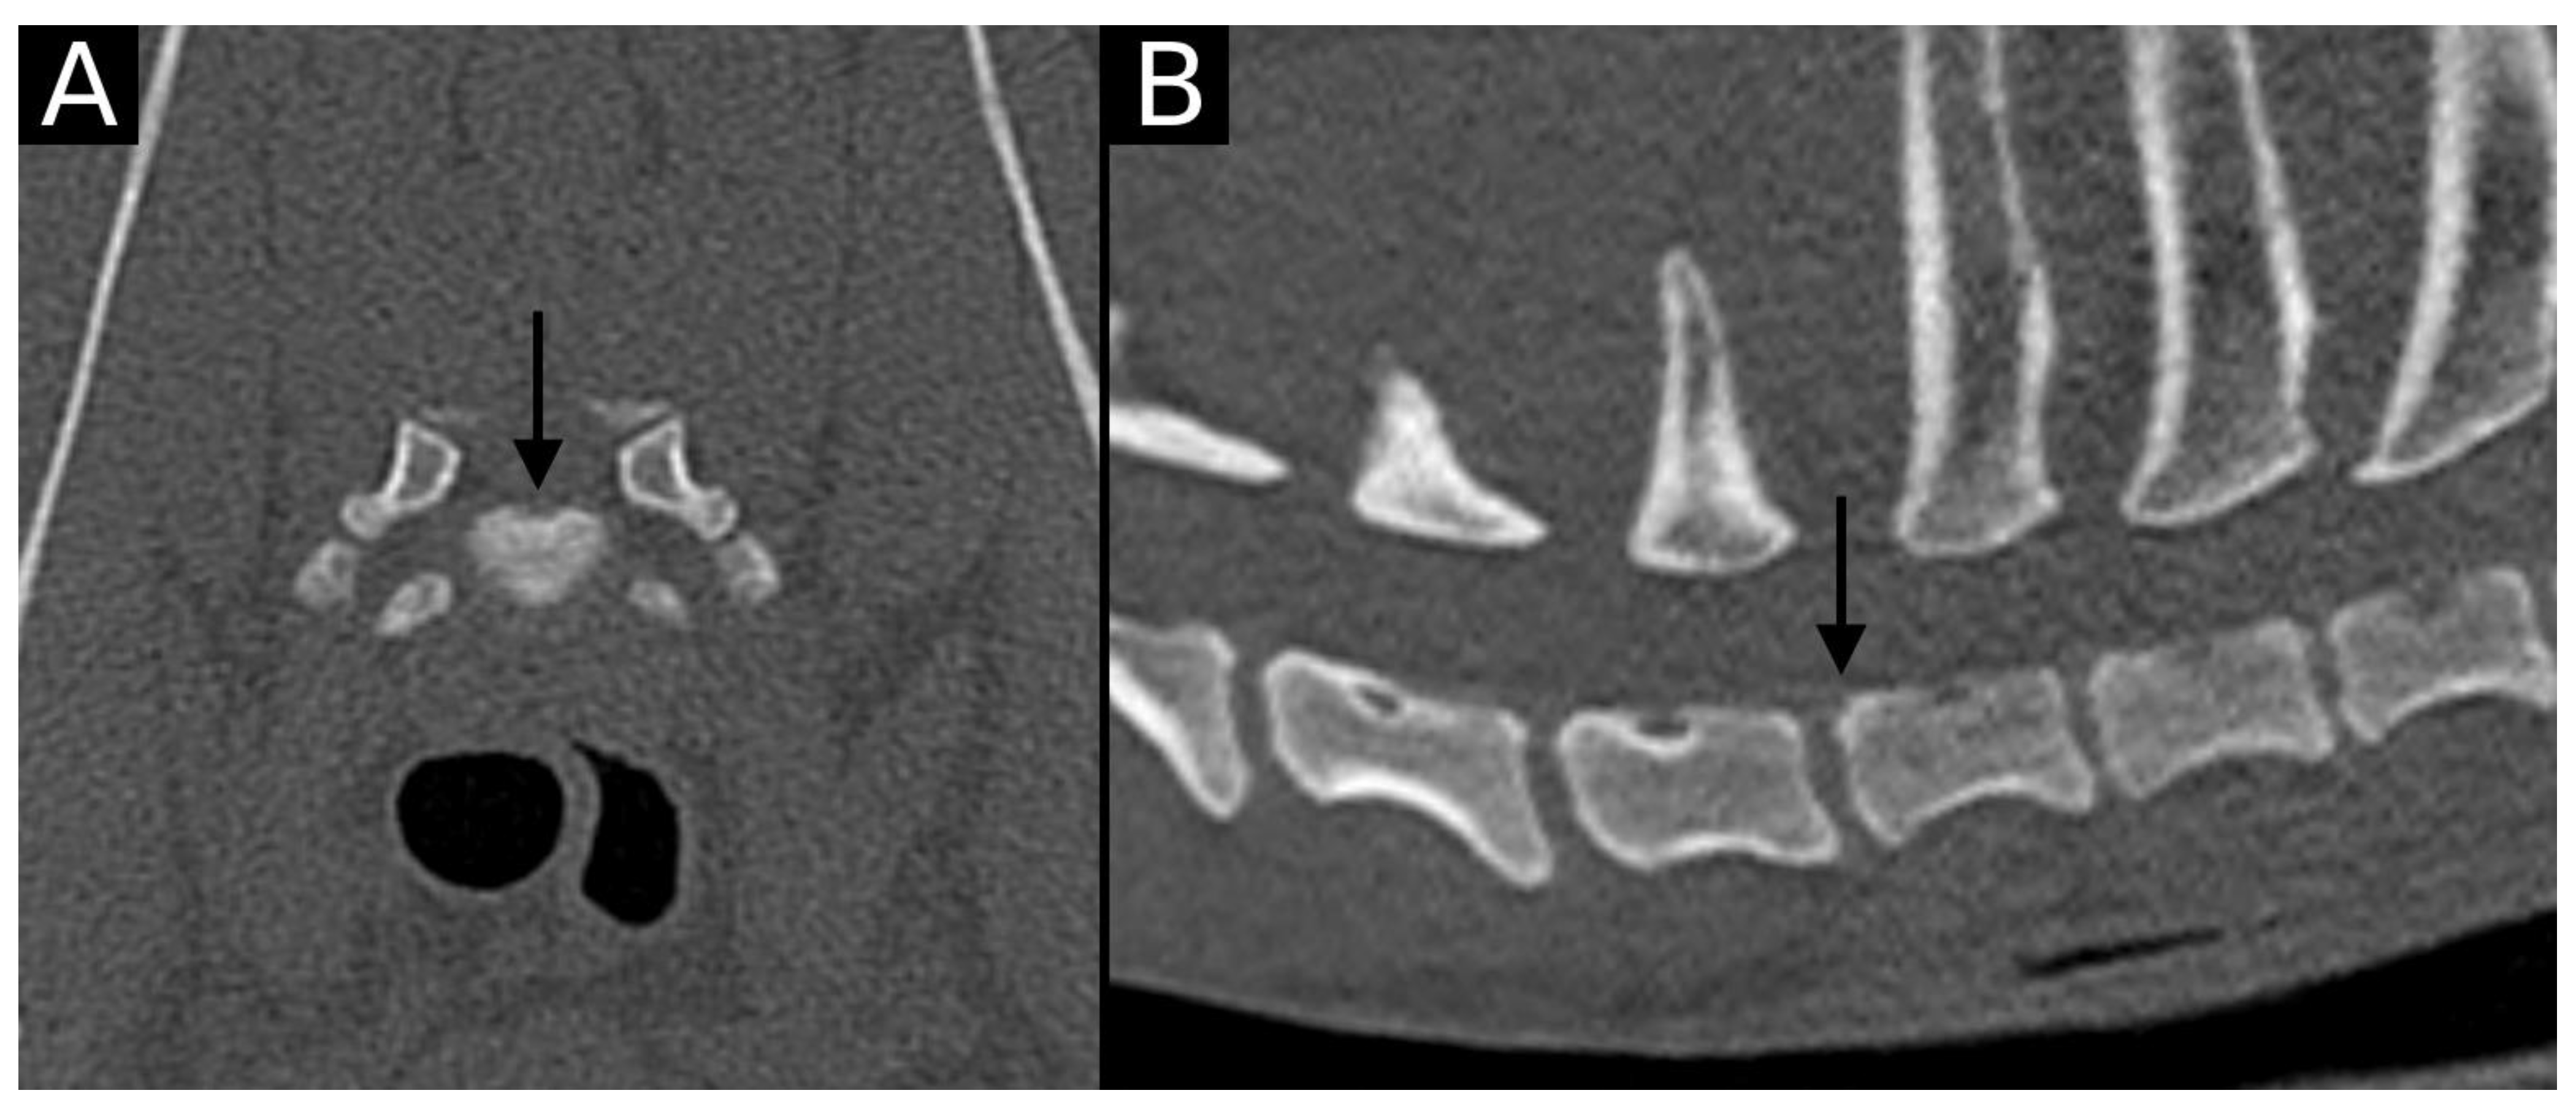

The junction between the endplates and intervertebral discs of the cervicothoracic junction (C6–C7, C7–T1 and T1–T2) were evaluated for the presence of alterations. When present, they were also graded and scored for EPJA, IVD herniation, spondylosis deformans, endplate sclerosis, articular process joint osteoarthrosis, and the presence of vertebral morphological abnormalities. The scoring system for endplate junction alterations and other spinal abnormalities was based on the proposed scoring by Tellegen et al. [13] for presumed EPJF at the lumbosacral spine. Endplate junction alterations were classified into four types (A, B, C, D): Type A involved presence of irregularity of the endplate margins without an obvious free fragment (Figure 1 and Figure 2); Type B involved avulsion evidenced by a thin rim of bone associated with a defect in the dorsal edge of the adjacent endplate (Figure 3); Type C included frank avulsion of a bony fragment (Figure 4) and Type D included presence of bony avulsion of both endplates. If EPJA was present, location (dorsal or ventral) and lateralization of the defect were also recorded. IVD herniation was graded from grades 0 to 3: grade 0 indicated no to mild (0–24%) herniation; grade 1 indicated mild to moderate (25–49%) herniation; grade 2 indicated moderate to marked (50–74%) herniation; grade 3 indicated marked herniation to complete obliteration (75–100%) of the vertebral canal by disc material. Spondylosis deformans was scored from grades 0 to 3: grade 0 indicated no enthesophytes; grade 1 indicated a small enthesophyte at the edge of the epiphysis that does not extend past the endplate; grade 2 indicated the presence of an enthesophyte that extends beyond the endplate but does not connect to the adjacent vertebra; and grade 3 indicated connecting enthesophytes from adjacent vertebrae forming a mineralized bridge. The other mentioned abnormalities (IVD mineralization, endplate sclerosis and articular process joint osteoarthrosis) were scored as present (1) or absent (0).

Figure 2. Transverse (A) and sagittal (B) reconstructions in bone algorithm. Mild contour irregularity and flattening lined by mild sclerosis are observed at the dorsal aspect of the T1 cranial endplate (arrow), consistent with EPJA Type A.